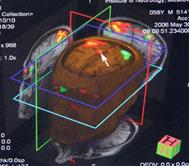

Рис.38. КТ-граммы ребенка с гидроцефалией тяжелой степени, ЛКИ=53%,

после операции нормализация внутричерепных взаимоотношений, ЛКИ= 3,2%.